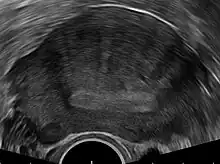

Adenomyosis can vary widely in the extent and location of its invasion within the uterus. As a result, there are no established pathognomonic features to allow for a definitive diagnosis of adenomyosis through non-invasive imaging. Nevertheless, non-invasive imaging techniques such as transvaginal ultrasonography (TVUS) and magnetic resonance imaging (MRI) can both be used to strongly suggest the diagnosis of adenomyosis, guide treatment options, and monitor response to treatment.[8] Indeed, TVUS and MRI are the only two practical means available to establish a pre-surgical diagnosis.[22]

Ultrasound

Transvaginal ultrasonography is a cheap and readily available imaging test that is typically used early during the evaluation of gynecologic symptoms.[22] Ultrasound imaging, like MRI, does not use radiation and is safe for examination of the pelvis and female reproductive organs.[23] Overall, it is estimated that transvaginal ultrasonography has a sensitivity of 79% and specificity of 85% for the detection of adenomyosis.[10]

Common transvaginal ultrasound findings are defined by the European MUSA group in 2015 [24] and are defined in 2022 by the MUSA group.[25] The ultrasound characteristics can be divided in direct and indirect features.

Direct features:

- myometrial cysts - pockets of fluid within the smooth muscle of the uterus

- Hyperechogenic islands - usually white endometrium islands within the myometrium

- Echogenenic subendometrial lines and buds - usually white lines and knobs attached to the endometrium, prtruding into the myometrium.

Indirect features:

- Globular, enlarged, and/or asymmetric uterus

- Fan shaped shadowing - differentiating from fibroids with linear shadowing

- Anterior/posterior wall asymmetry

- Translational vascularity - diffuse spread of small vessels within the myometrium

- Irregular or interrupted junctional zone - the borderline between the endometrium and myometrium

The power Doppler or Doppler ultrasonography function can be used during transvaginal ultrasonography to help differentiate adenomyomas from uterine fibroids.[22][26][27] This is because uterine fibroids typically have blood vessels circling the fibroid's capsule. In contrast, adenomyomas are characterized by widespread blood vessels within the lesion.[22] Doppler ultrasonography also serves to differentiate the static fluid within myometrial cysts from flowing blood within vessels.[22]

The junction zone (JZ), or a small distinct hormone-dependent region at the endometrial-myometrial interface, may be assessed by three-dimensional transvaginal ultrasound (3D TVUS) and MRI. Features of adenomyosis are disruption, thickening, enlargement or invasion of the junctional zone.[20] There is no consensus about the actual histology of the junctional zone and a recent review showed that the ultrasound, MRI and histology all define and describe the junctional zone differently.[28]